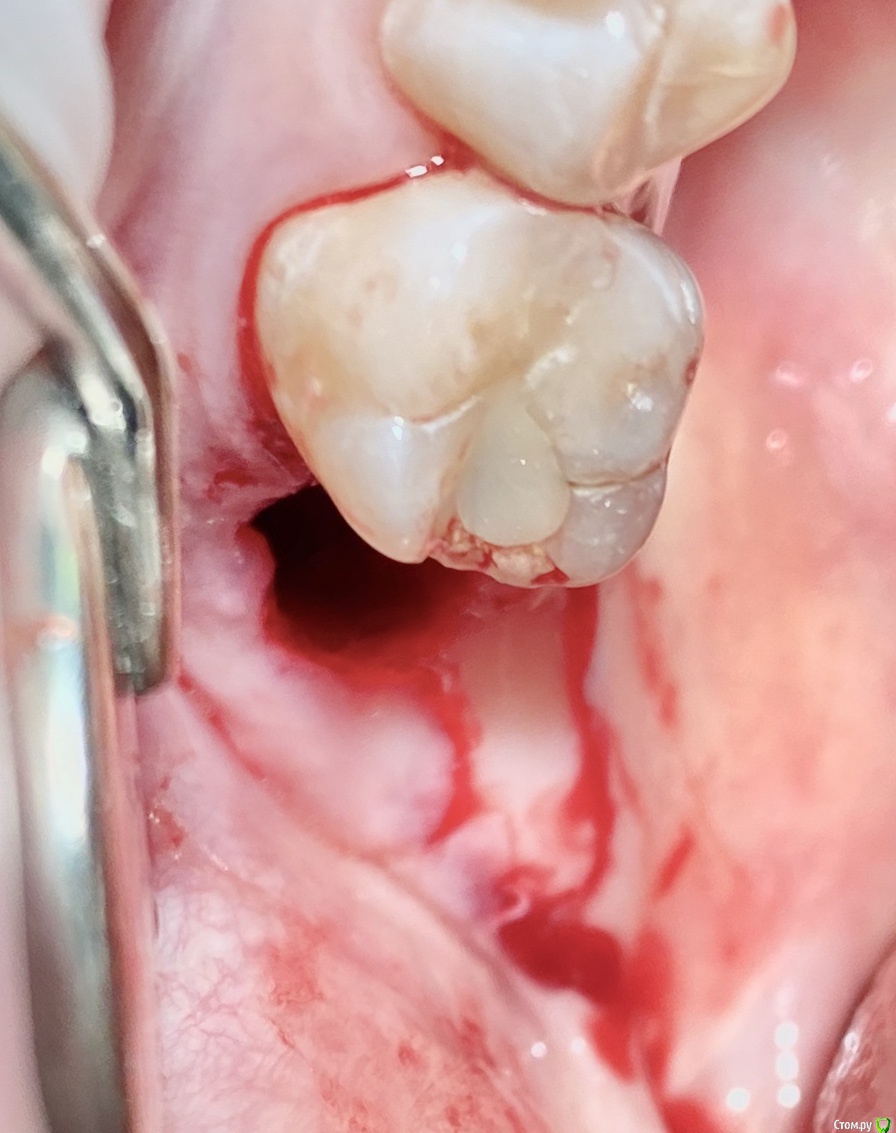

колесников Опубликовано 9 сентября, 2020 Поделиться Опубликовано 9 сентября, 2020 Бугор -это не только то ,что очевидно на поверхности 1 Ссылка на комментарий

колесников Опубликовано 11 сентября, 2020 Поделиться Опубликовано 11 сентября, 2020 Перемещение бугра для закрытия лунки. Вестибулярно прикрепленную не смещаем. Вестибулярно компактной пластинки нет 9 Ссылка на комментарий